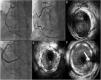

(A) Electrocardiogram on admission; (B and C) coronary angiography showing spontaneous dissection of the left anterior descending (LAD) artery occupying all of the mid and distal segments and extending to the posterolateral branch; (D) coronary angiography performed after cardiac arrest 30 hours after admission, revealing apparent progression of the LAD dissection; (E and F) intravascular ultrasound images of an intramural hematoma extending from the proximal LAD (arrow).

During day 1 of hospital stay, the patient suffered cardiac arrest in asystole preceded by severe bradycardia, from which he recovered after two cycles of advanced life support. It was decided to place a temporary pacemaker and to repeat coronary angiography with IVUS, which confirmed the positioning of the guidewire in the true lumen and revealed apparent progression of the LAD dissection to the proximal third of the artery. Given the patient’s hemodynamic and electrical instability, it was decided to perform angioplasty of the LAD and to place a 3.50mm×23mm Absorb™ bioresorbable vascular scaffold in the proximal segment overdilated with a 4.00mm×20mm non-compliant balloon. Distal flow in the vessel remained at TIMI 2 (Figure 4). Echocardiography performed on day 1 showed moderately impaired global systolic function (left ventricular ejection fraction ∼45%) and akinesis of the apex and apical segments and hypokinesis of the mid segment of the interventricular septum and anterior wall. On day 3, as there had been no further episodes of electrical instability, the temporary pacemaker was removed. Despite hemodynamic, electrical and clinical stability, laboratory tests showed no decrease in myocardial necrosis markers, which varied over the course of hospitalization. Accordingly, after multidisciplinary discussion, on day 6 it was decided to perform angioplasty of the mid and distal segments with predilation with a 2.5mm×30mm balloon followed by placement of two Absorb™ scaffolds, 3mm×28mm and 2.5mm×23mm. As this was an area of myocardial bridging, a drug-eluting stent (2.5mm×38mm XIENCE Alpine™) was implanted overlapping the scaffolds, with a good final result (Figure 4).

(A) Passage of the floppy guidewire to the distal left anterior descending artery; (B and C) implantation of a 3.50mm×23mm AbsorbTM bioresorbable vascular scaffold; (D and E) intravascular ultrasound images after implantation of the Absorb scaffold showing good apposition and expansion, sealing the proximal entry to the dissection; (F) implantation on day 6 of two AbsorbTM scaffolds (3mm×28mm and 2.5mm×23mm) and a XIENCE AlpineTM drug-eluting stent (2.5mm×38mm), with a good final angiographic result.